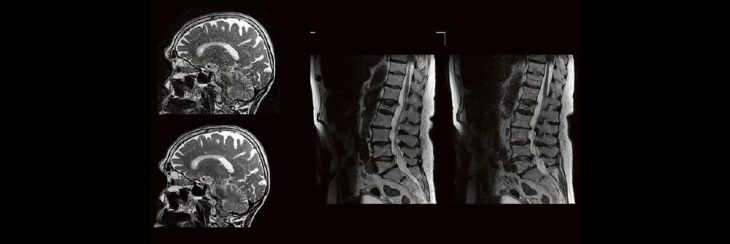

Professor Dr. med. Marc Brockmann WEITERENTWICKLUNGEN VON KOPF BIS FUSS BEIM VC Oberstarzt Dr. med. Stephan Waldeck DEEP-LEARNING-REKONSTRUKTION IN DER NEURORADIOLOGIE Die CT ist ein essentielles Routine-Verfahren in der Neuroradiologie. Bei steigender Bildqualität konnte die Röntgendosis mit neuen Technologien in der letzten Dekade deutlich gesenkt werden, was für die zielgerichtete und möglichst schonende Behandlung vonRead more about DEEP-Learning-Rekonstruktion in der Neuroradiologie (Webinar | Online)[…]